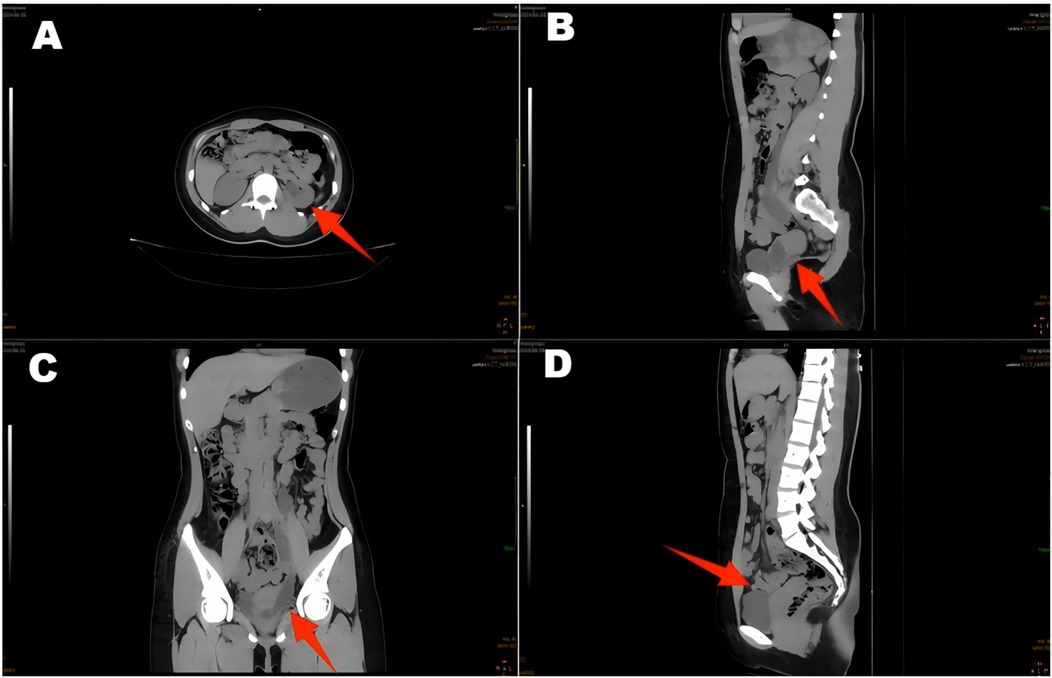

A 22-year-old female patient presented with persistent urinary incontinence since infancy, spanning over two decades. The patient's perineal area remains persistently moist, requiring 3–4 diaper changes daily. The patient had no significant past medical history and no familial history of similar conditions. No history of surgery or childbirth at the time of consultation. The patient grew up in an orphanage after being abandoned as an infant. Due to this socially vulnerable background and lack of longstanding familial support, her condition was neither brought to medical attention nor formally evaluated in childhood or adolescence. Clinical examination revealed thickening of the external urethral orifice, with a suspected vaginal opening measuring approximately 0.7 centimeters in diameter. To determine the cause of the patient's long-standing urinary incontinence, we conducted a series of systematic imaging and endoscopic investigations. Initial multi-slice CT imaging revealed compensatory enlargement of the left kidney with hydronephrosis affecting the entire renal pelvis and ureter. A cystic, low-density lesion connecting the distal ureter to the anterior vaginal wall was identified, suggesting a possible ectopic ureteral opening into the vagina (Figure 1). Magnetic resonance imaging of the urinary system confirmed bilateral renal abnormalities with double ureteral malformations, hydronephrosis on the left side, and ectopic opening of the left ureter into the anterior vaginal wall, accompanied by a bicornuate uterus. Intravenous urography (IVU) further confirmed bilateral ureteral anomalies on the right side, whilst the dilated left ureter exhibited a bifurcated pattern in its middle and upper segments, ultimately converging near the bladder, thus ruling out complete duplication (Figure 2). Cystoscopy revealed two openings in the right ureter consistent with a duplicated ureteral anomaly. An ectopic opening of the left ureter was identified near the external urethral orifice on the anterior vaginal wall. In contrast, the ureteral opening on the ipsilateral side of the bladder trigone was absent (Figure 3). It should be noted that a limitation in this case was the absence of renal scintigraphy to assess left renal segmental function. This examination is crucial for identifying such congenital anomalies, serving as a key basis for guiding clinical decision-making and selecting the surgical approach. The patient underwent transurethral cystoscopy and left ureter cystostomy under general anesthesia. Intraoperatively, the left ureteral orifice was found to be ectopically located on the anterior vaginal wall near the external urethral orifice. Additionally, approximately 2 cm above the external iliac artery, the ureter exhibited thickened adhesions spanning about 8 cm in length (Figure 4). The definitively identified ectopic opening location precisely matched the preoperative cystoscopy localization, confirming the diagnosis of congenital ureterovaginal fistula. Ureter cystostomy was performed by creating a subcutaneous tunnel, excising the redundant ureter segment, and anastomosing it to the bladder mucosa, with a double-J stent placed. Postoperative urinary incontinence symptoms were completely resolved, and the patient was discharged successfully on the fourth postoperative day. During the two-month follow-up period, the patient reported having completely discontinued the use of urinary pads. Ultrasound follow-up revealed complete resolution of left hydronephrosis with no significant ureteral dilatation observed. After two months postoperatively, the double-J stent was removed via cystoscopy, and the patient's urinary function returned to normal.

Figure 1. CT scan of the ureter shows hydronephrosis of the left renal pelvic ureter (A,C,D), with a suspected terminal ureter connected to a cystic hypodense shadow of the vagina (B).